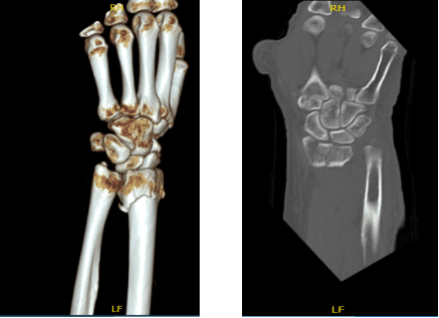

The patient is a 63 year-old female seen in the office with left wrist pain due to falling on the wrist. She was seen at Mather by Dr. Karkare where reduction was done. She got a CT done.

CT were reviewed and discussed by the doctor; there is a comminuted fracture of the distal radius with intra-articular extension where displacement measures approximately 1 mm. Maximal fracture displacement measures approximately 9 mm.

Approximately 20 degrees of palmar angulation are present. A displaced fracture of the ulnar styloid is also identified. Mild degenerative changes are present at the triscaphe and first carpometacarpal joints.